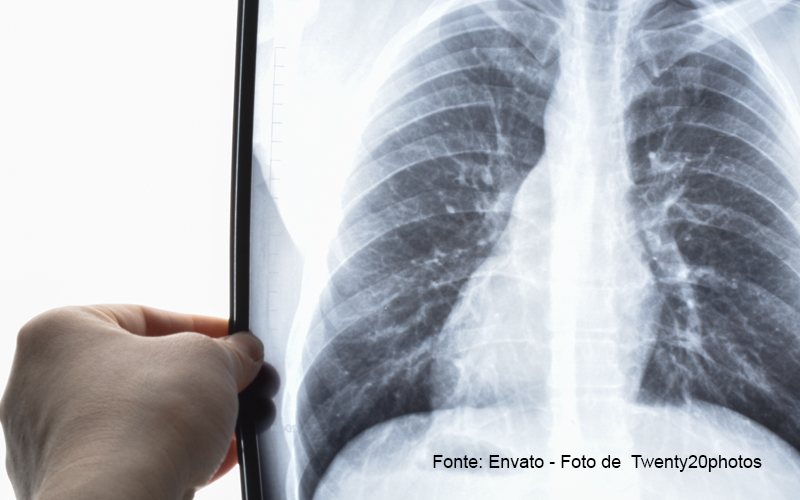

A pneumonia é uma infecção que afeta os pulmões. A doença considerada grave pode ser provocada por fungos, bactérias ou vírus e se não for tratada de forma precoce, pode matar. Gripes e Covid-19 podem aumentar as chances de infecções secundárias. (G1)